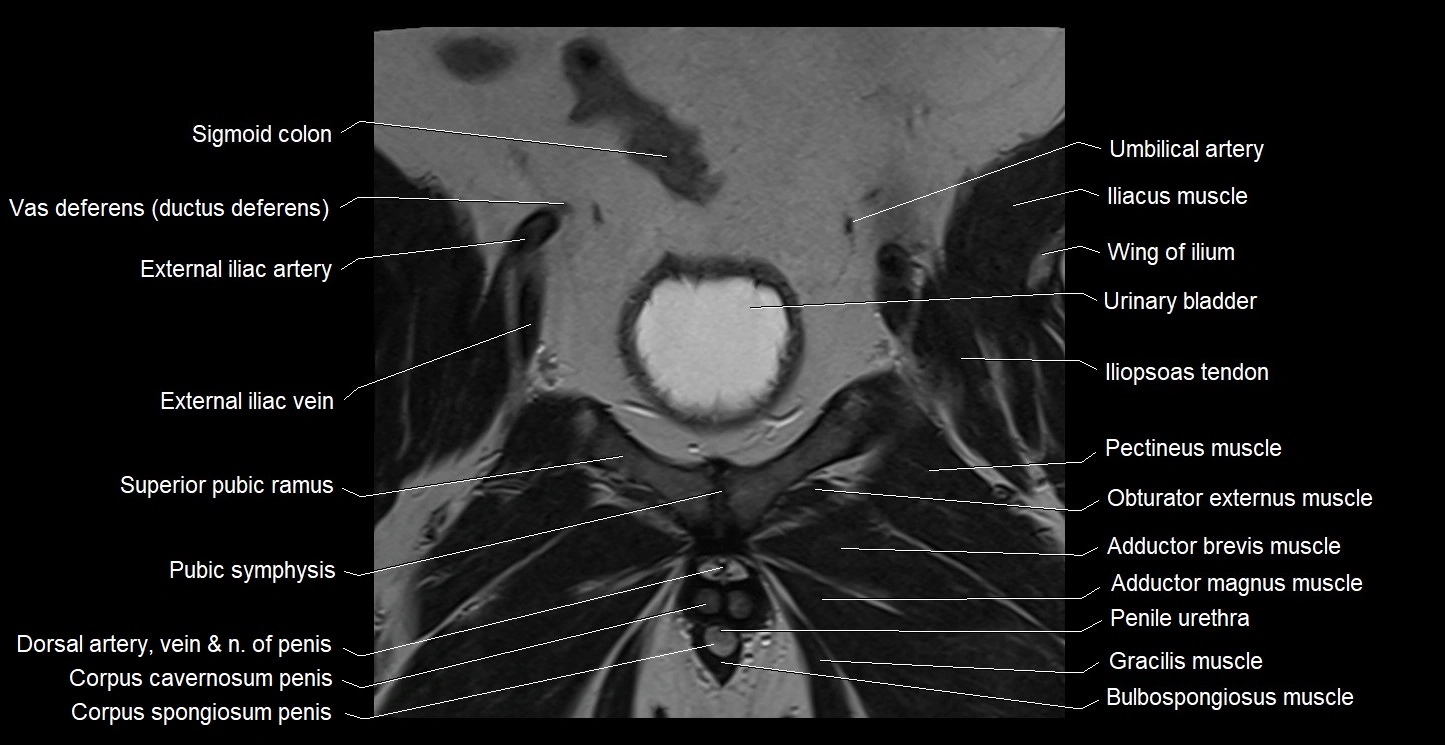

- Adductor brevis muscle

- Adductor magnus muscle

- Bulbospongiosus muscle (Male)

- Corpus spongiosum

- External iliac artery

- External iliac vein

- Gracilis muscle

- Iliopsoas muscle

- Iliopsoas tendon

- Obturator externus muscle

- Pectineus muscle

- Penile urethra

- Pubic symphysis

- Sigmoid colon

- Superior pubic ramus

- Umbilical artery

- Urinary bladder

- Vas deferens